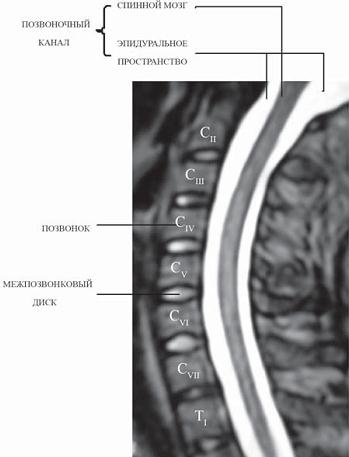

В этой основной части осевого скелета человека различают шейный, грудной, поясничный, крестцовый и копчиковый отделы. Рассмотрим более подробно эти отделы и наиболее типичное количество их позвонков. Шейный отдел является самым подвижным. В нём располагаются 7 позвонков. Латинское название vertebrae cervicales — позвонки шейные (vertebra — позвонок; cervix — шея). В медицинских документах позвонки этого отдела помечаются латинской буквой «С» — сокращение от слова cervicales, а приписываемый к букве индекс, к примеру СI, СII, СIII и т. д., означает номер позвонка — первый шейный позвонок (СI второй шейный позвонок (СII) и т. д. ![]() Рисунок № 7. Отделы позвоночника На данные позвонки приходится меньше нагрузки по сравнению с нижележащими отделами позвоночного столба, поэтому и выглядят они более «миниатюрно». Особого внимания заслуживают первые два шейных позвонка, которые значительно отличаются от других (их ещё называют атипичными позвонками). Они хоть и маленькие по размерам, но самые ответственные работники, которые отвечают за подвижное сочленение с черепом. Почти как люди, которые приближены к самым верхам органов власти и отвечают за… Ну, не будем об этом. Поэтому I и II шейные позвонки имеют не только особую форму, отличаясь по своему строению от других позвонков, но и персональные названия: атлант и эпистрофей. МРТ № 1 ![]() На магнитно-резонансной томографии (МРТ) № 1 — шейный отдел позвоночника, в относительно нормальном состоянии. Шейный отдел позвоночника должен иметь нормально выраженный физиологический лордоз, не должно быть гиполордоза или гиперлордоза, а так же кифотических деформаций. Ширина спинного мозга: сагиттально > 6–7 мм 1. Сагиттальный размер позвоночного канала на уровне: СI ≥ 21 мм СII ≥ 20 мм СIII ≥ 17 мм CIV-CVII = 14 мм 2. Высота межпозвонковых пространств: СII < СIII < СIV < СV < СVII ≥ СVII 3. Ширина спинномозгового канала: поперечный диаметр на уровне ножек: > 20–21 мм ![]() Рисунок № 8. Первый шейный позвонок — атлант (atlas). Вид сверху 1 — позвоночное отверстие; 2 — задний бугорок; 3 — задняя дуга; 4 — борозда позвоночной артерии; 5 — отверстие поперечного отростка; 6 — верхняя суставная ямка; 7 — поперечный отросток; 8 — латеральная масса; 9 — ямка зуба; 10 — передний бугорок; 11 — передняя дуга. Имя Атлант каждый, наверное, слышал ещё в детстве из цикла античных легенд о богах Олимпа. Правда, сказания о последних мне больше напоминает то, о чём когда-то давно говорил римский поэт Гораций: «Decipimur specie recti», что означает «Мы обманываемся видимостью правильного». Так вот, согласно древнегреческой мифологии, был такой титан Атлант (брат Прометея), который в наказание за участие в борьбе титанов против олимпийских богов держал по приказу Зевса небесный свод на своих плечах. В честь Атланта (греч. atlas) и был назван первый шейный позвонок. Любопытно, что данный позвонок лишён остистого и суставных отростков, не имеет даже тела и вырезок. Он состоит из двух дужек, соединённых между собой боковыми костными утолщениями. Всё как бывает у людей в вертикали власти, мол, среди слепых и кривой — царь. Своими верхними суставными ямками атлант прикрепляется к мыщелкам (костным выступам, входящим в состав сочленения) затылочной кости. Последние, так сказать, ограничивают степень свободы (подвижности) атланта, чтобы этот позвонок знал своё место и за рамки дозволенного не выходил. ![]() Рисунок № 9. Второй шейный позвонок — эпистрофей (осевой — axis). Вид сзади и сверху 1 — зуб осевого позвонка; 2 — задняя суставная поверхность;3 — верхняя суставная поверхность; 4 — тело позвонка; 5 — поперечный отросток; 6 — отверстие поперечного отростка; 7 — нижний суставной отросток; 8 — остистый отросток; 9 — дуга позвонка Второй шейный позвонок — эпистрофей. Так его назвал Андреас Везалий — врач, основоположник научной анатомии, живший в эпоху Возрождения. Греческое слово epistrepho означает «поворачиваюсь, вращаюсь». Латинское название второго шейного позвонка — axis (ось), то есть осевой. Этот позвонок не менее важный, чем атлант, если говорить с юмором, то это ещё тот «изворотливый гусь». Он имеет костный вырост — отросток, похожий на зуб (называется зубовидный отросток), вокруг которого вращается атлант вместе с сочленяющимся с ним черепом. Если проводить параллели с людской жизнью, то второй шейный позвонок похож на тех людей, которые держатся у власти за счёт компромата на своё начальство. Не зря в народе говорят, «этот человек зуб точит на начальство». Вот такой он, эпистрофей, маленький, незаметный, а держит всю голову. Однако как бы эти позвонки не называли, а оба они составляют уникальный механизм, благодаря которому человек может совершать разнообразные движения головой, делать те же повороты, наклоны, в том числе и бить челом, когда органам власти подаёт свою челобитную. ![]() Рисунок № 10. Типичный шейный позвонок (CIII—CVII). Вид сверху 1 — позвоночное отверстие; 2 — дуга позвонка; 3 — остистый отросток; 4 — верхний суставной отросток; 5 — нижний суставной отросток; 6 — поперечный отросток; 7 — задний бугорок поперечного отростка; 8 — передний бугорок; 9 — тело позвонка; 10 — поперечное отверстие. Вообще шейный отдел — это «особый отдел» сотрудников-позвонков, которые в том числе несут ответственность за безопасность головы. Благодаря своей уникальной конструкции и работе, шейный отдел обеспечивает возможность для головы следить, держать под контролем (зрительным, естественно) достаточно обширную часть пространственного кругозора при наименьшей подвижности «рабочего» организма в целом. Кроме того, поперечные отростки всех шейных позвонков имеют особые отверстия, отсутствующие в других позвонках. Эти отверстия в совокупности, при естественном положении шейных позвонков, образуют костный канал, в котором проходит позвоночная артерия, кровоснабжающая головной мозг. |